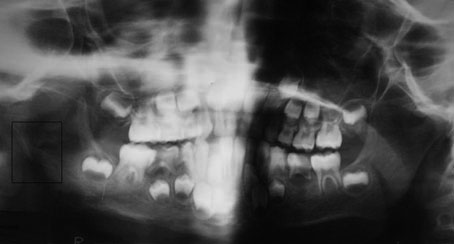

L’orthopantomogramme a montré un foyer ostéolytique irrégulier, au contour plus ou moins précis par rapport à l'os sain adjacent avec fracture sous condylienne basse (fig. 1).